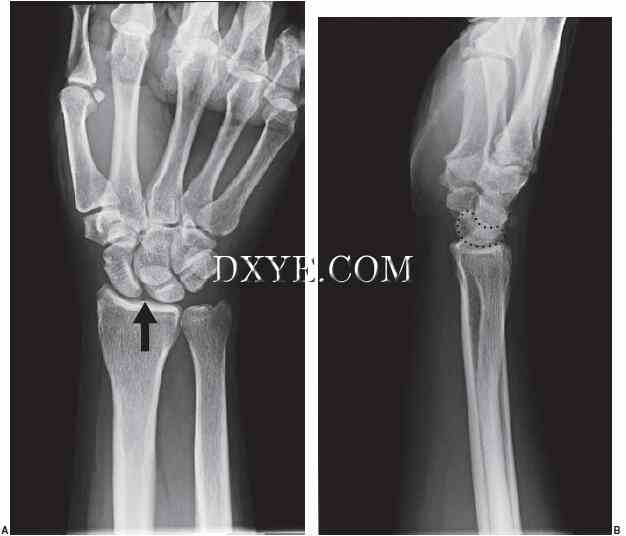

3.jpg

图 70.3.  AP和侧腕X线腕背侧不稳(DISI)。 A. 舟月扩大显示AP视图箭头。 B. 背侧的月形在侧面看有白色圆点。